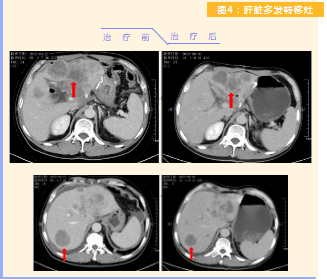

患者完成1周期治療后,上腹部疼痛癥狀基本消失,梗阻性黃疸癥狀緩解,腫瘤指標(biāo)下降(圖1),肺部多發(fā)轉(zhuǎn)移灶消失和縮小(圖2),雙肺門淋巴結(jié)縮?。▓D3),肝臟多發(fā)轉(zhuǎn)移灶縮小(圖4)。